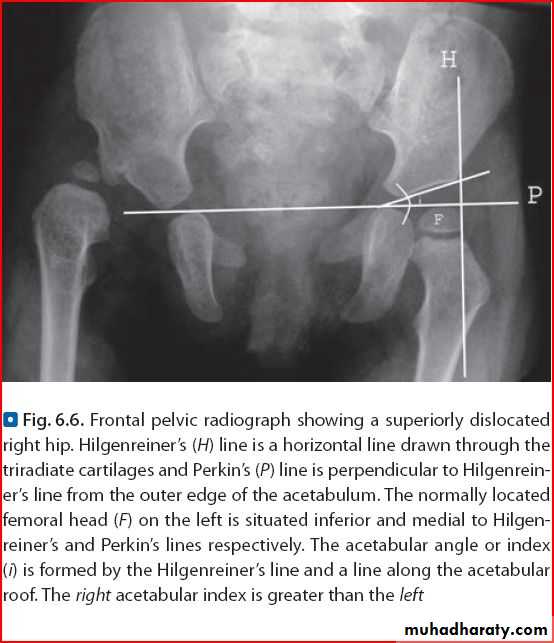

DDH

X ray show shenton line and perkin line

, us show head of femur outside ihe accetabular groove for grading